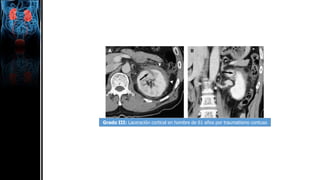

Paciente con herida por arma de fuego en la región lumbar. Se observa fractura del

tercio medio renal asociada con un hematoma subcapsular (flecha).

Grado III: Laceración cortical en hombre de 61 años por traumatismo contuso

Grado IV: Infarto segmentario en hombre de 34 años tras traumatismo contuso